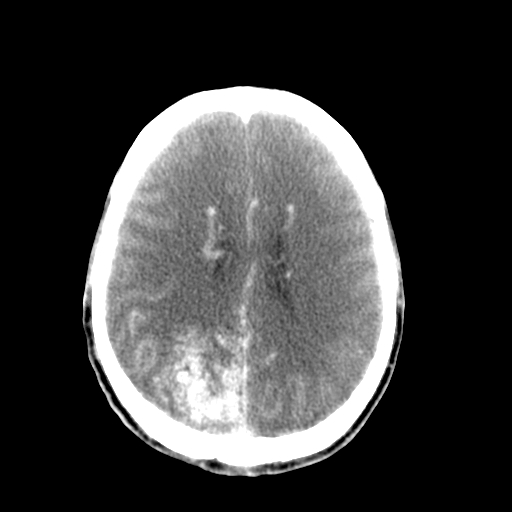

标题: CT17002:M48Y,血管畸形,血管瘤,请鉴赏! [打印本页]

标题: CT17002:M48Y,血管畸形,血管瘤,请鉴赏!

男48y,头痛多年,加重一天!

典型的血管畸形---avm  -----右侧枕顶叶及侧脑室三角区等高混杂密度影夹杂少许低密影显示,无明显水肿,增强可见明显的供血动脉与引流静脉显示